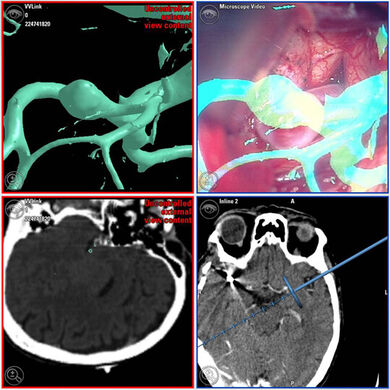

Hierzu gehört die Konzeption und Implementierung eines Softwaresystems, das anatomische und funktionelle Daten visuell integriert. Neben rein morphologischen Bilddaten wie Magnetresonanztomographie (MRT) oder Computertomographie (CT) betrifft dies z.B. funktionelle Magnetresonanz-Tomographie (fMRT), Electroenecephalographie (EEG), Magnetoencephalographie (MEG) sowie anatomische Atlasinformationen. Es besteht u.a. die Möglichkeit, relevante Strukturen zu segmentieren sowie Streckenlängen und Volumina zu quantifizieren. Nach der Planungsphase kann das System während der Operation mit dem Navigationssystem sowie elektrophysiologischen Untersuchungen gekoppelt werden. Der Operateur hat dadurch die Möglichkeit, die visualisierten multimodalen Daten unmittelbar während des operativen Eingriffs zu berücksichtigen, ohne seinen gewohnten Arbeitsablauf zu beeinträchtigen.

Darüber hinaus werden diagnostische Daten auf ihre Eignung für die intraoperative Verwendung untersucht. Derzeit bildet die Integration von elastisch registrierten 3D-Angiographiedaten einen Schwerpunkt. In diesem Kontext spielt die „Augmented Reality“, d.h. die Überblendung des realen Bildes des Operationssitus durch das OP-Mikroskop mit der zugehörigen computergenerierten Visualisierung eine wichtige Rolle.